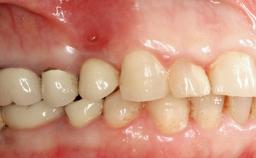

The fracture of an implant after it has been restored is one of the most severe complications. It most frequently occurs in partially edentulous jaws (1.5%). Most implant fractures involve implants with a diameter of 3.75 mm made of commercially pure titanium (Eckert 2010). Unfortunately, many cases are not reported or documented by the clinicians involved in resolving the problems created by the fracture. This case report describes the management of an implant fracture at site 36 in a middle-aged male patient. The implant had been restored with a screw-retained metal-ceramic crown.

Case Type Single-Tooth Space

Jaw Mandible

Area Posterior

# of Teeth 1

# of Implants 1